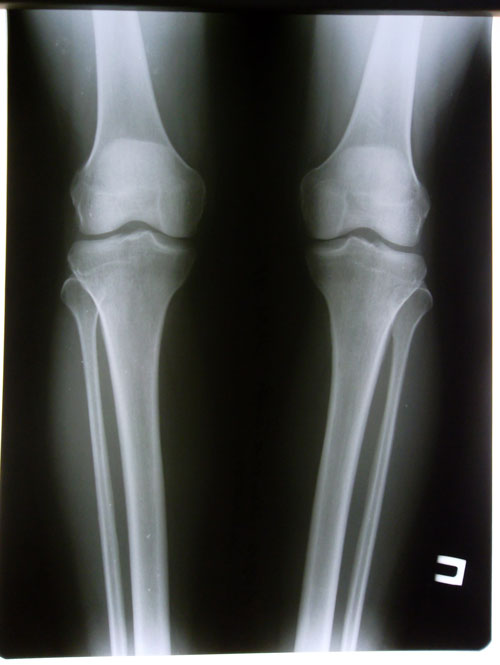

Дата операции 16.06.2014г.

Дата снятия аппаратов 04.11.2014г.

Срок лечения 138 дней.

рентген в день снятия аппаратов.